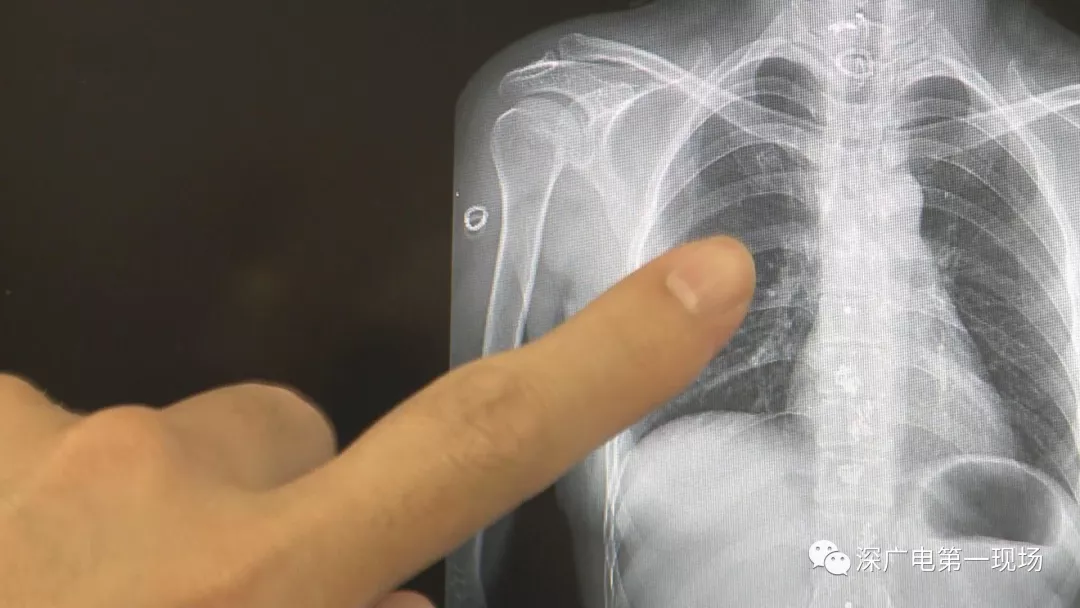

從X光影像圖片中可以看到

患者周身布滿了彈簧圈

深圳大學總醫院神經外科副主任醫師陳富勇介紹,當時檢查的時候發現,該患者從頭部到腿部,基本上每個地方都有彈簧,很難數清具體數目。